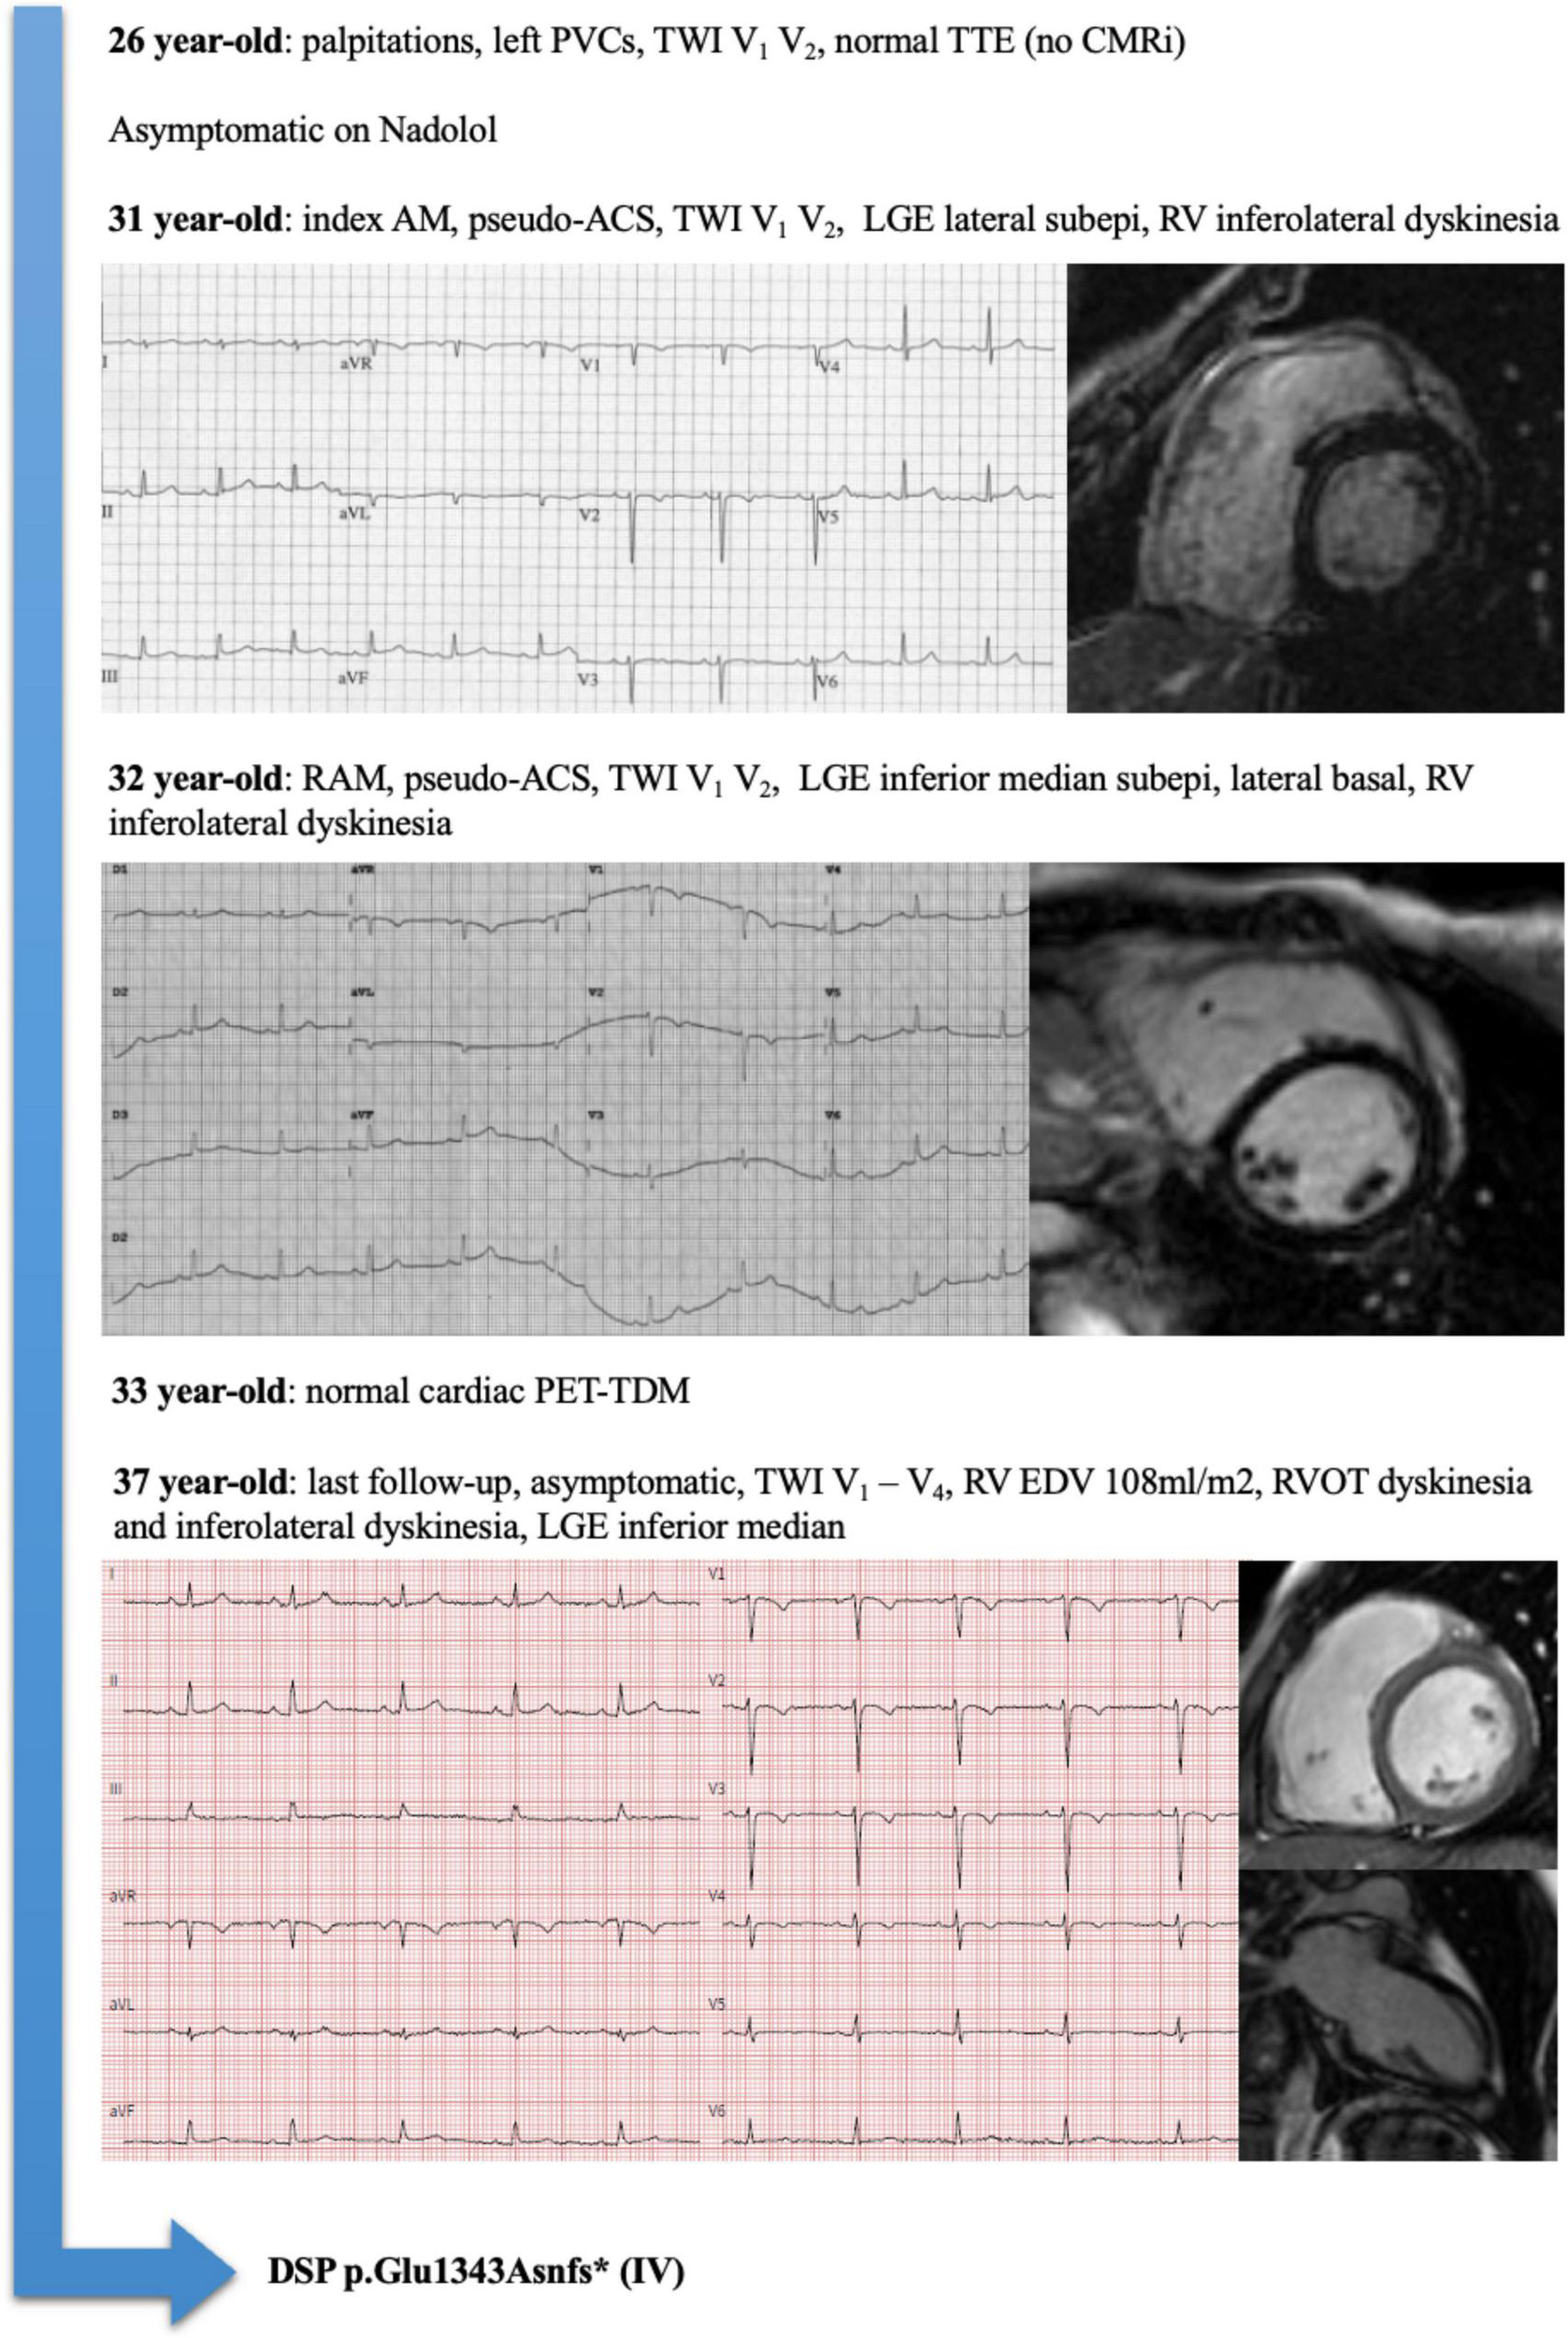

Considering the 14 patients with RAM and ACM phenotype at the end of follow-up, family history had a sensitivity of 88% and a positive predictive value of 100% for the presence of an underlying genetic mutation. An illustrative example of a patient (number 5) with RAM, ACM phenotype, and DSP mutation is illustrated in Figure 1. A proposed model for the association between RAM and genetic ACM is illustrated in Figure 2.

FIGURE 1

Representative example of a patient (Pt#5) with recurrent acute myocarditis (RAM), arrhythmogenic cardiomyopathy (ACM) phenotype, and Desmoplakin (DSP) mutation.

| 5 | Brother SCD Mother HCM | 31 | Pseudo-ACS | TWI V1–V2 | LGE lateral (subepi), RV inferolateral dyskinesia | 32 | Pseudo-ACS | TWI VI–V2±V3 | LGE inferior median, lateral basal (subepi), RV dyskinesia | 0 |

| 5 | Brother SCD Mother HCM |

35 | 0 | TWI VI–V4 | Right PVCs | RV EDV 108 ml/m2 and RVOT dyskinesia, LGE inferior median | 2M lm | 1M 0m | Yes | DSP p.Glul343Asnfs* (IV) |